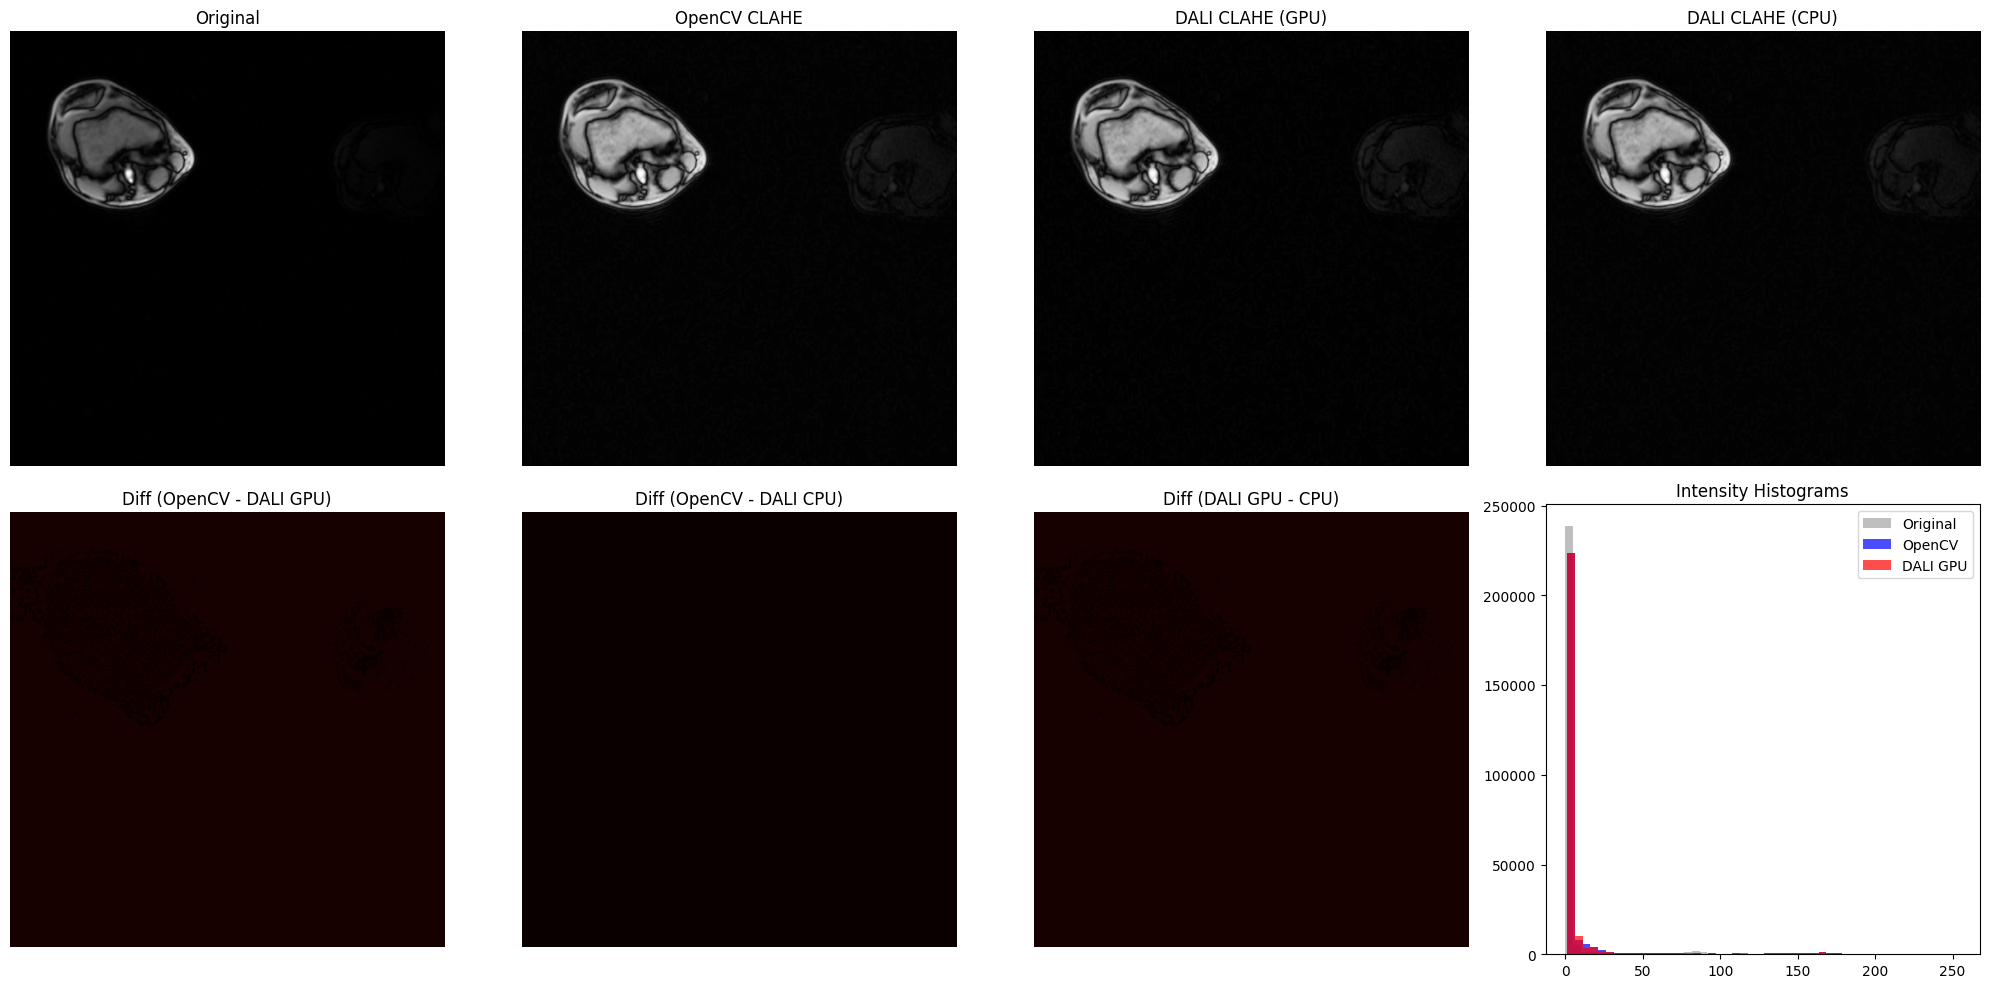

[7]:

# Difference Maps and Intensity Histograms

diff_opencv_dali_gpu = np.abs(

opencv_result.astype(float) - dali_gpu_np.astype(float)

)

diff_opencv_dali_cpu = np.abs(

opencv_result.astype(float) - dali_cpu_np.astype(float)

diff_dali_gpu_cpu = np.abs(

dali_gpu_np.astype(float) - dali_cpu_np.astype(float)

fig, axes = plt.subplots(2, 4, figsize=(20, 10))

# Top row: images

axes[0, 0].imshow(mri_array.squeeze(), cmap="gray")

axes[0, 0].set_title("Original")

axes[0, 0].axis("off")

axes[0, 1].imshow(opencv_result.squeeze(), cmap="gray")

axes[0, 1].set_title("OpenCV CLAHE")

axes[0, 1].axis("off")

axes[0, 2].imshow(dali_gpu_flat, cmap="gray")

axes[0, 2].set_title("DALI CLAHE (GPU)")

axes[0, 2].axis("off")

axes[0, 3].imshow(dali_cpu_flat, cmap="gray")

axes[0, 3].set_title("DALI CLAHE (CPU)")

axes[0, 3].axis("off")

# Bottom row: difference maps and histogram

axes[1, 0].imshow(diff_opencv_dali_gpu.squeeze(), cmap="hot", vmin=0, vmax=50)

axes[1, 0].set_title("Diff (OpenCV - DALI GPU)")

axes[1, 0].axis("off")

axes[1, 1].imshow(diff_opencv_dali_cpu.squeeze(), cmap="hot", vmin=0, vmax=50)

axes[1, 1].set_title("Diff (OpenCV - DALI CPU)")

axes[1, 1].axis("off")

axes[1, 2].imshow(diff_dali_gpu_cpu.squeeze(), cmap="hot", vmin=0, vmax=50)

axes[1, 2].set_title("Diff (DALI GPU - CPU)")

axes[1, 2].axis("off")

# Intensity histograms

axes[1, 3].hist(

mri_array.ravel(), bins=50, alpha=0.5, color="gray", label="Original"

opencv_result.ravel(), bins=50, alpha=0.7, color="blue", label="OpenCV"

dali_gpu_np.ravel(), bins=50, alpha=0.7, color="red", label="DALI GPU"

axes[1, 3].set_title("Intensity Histograms")

axes[1, 3].legend()

plt.tight_layout()